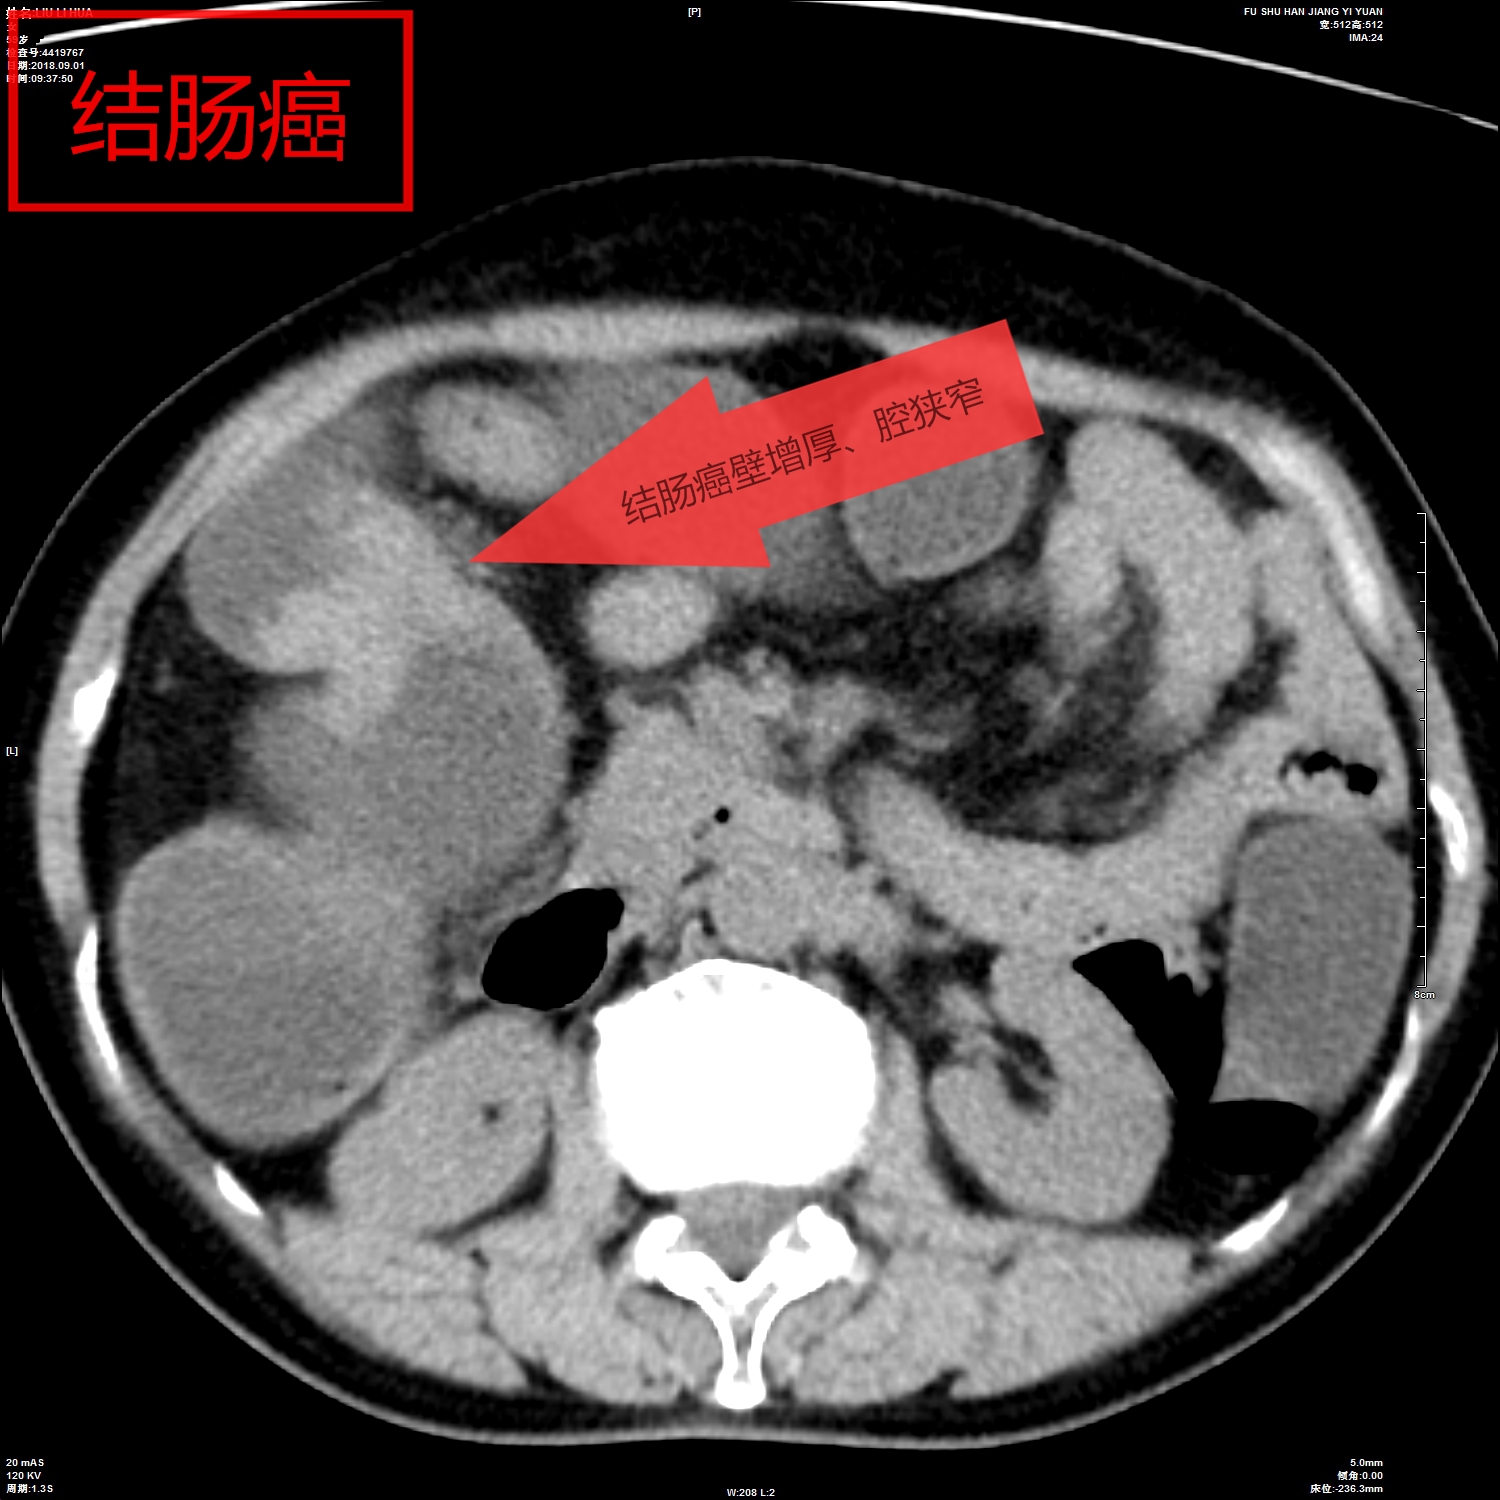

我院影像科从2018年开始,利用CT、MR分辨率高、成像方法多的特点,开展胃肠快速充盈低张CT、MR检查技术,通过多序列、多窗位、多方位检查,对肠壁、及其腔内腔外病变连续观察,取得了很好的检查诊断效果。检查技术成熟安全、无创,确诊了多例胃癌、胃息肉、结肠癌、肠先天性发育旋转不良等胃肠道疾病,并对肿瘤的转移及周围结构进行评估,为患者进一步综合治疗,打下了坚实的基础。

胶囊内镜检查具有移动的不可控性,常规消化道纤维内镜存在视野局限、有创,通过障碍无法评估腔外解剖与病变,对通过障碍的病灶仅能显示病变近端,然而胃肠道快速充盈低张影像检查技术具有无创、反复观察、定位准确的优势。它可通过充分的肠道准备,虚拟内镜及多方位重建,可从任意角度和方式对病灶进行观察,并能从狭窄、梗阻处两端观察肠腔的解剖和病变,可靠的显示了病变部位和范围,同时提供腔内外的情况并能对淋巴转移、血管癌栓、远处转移进行评估。

影像图片(一)